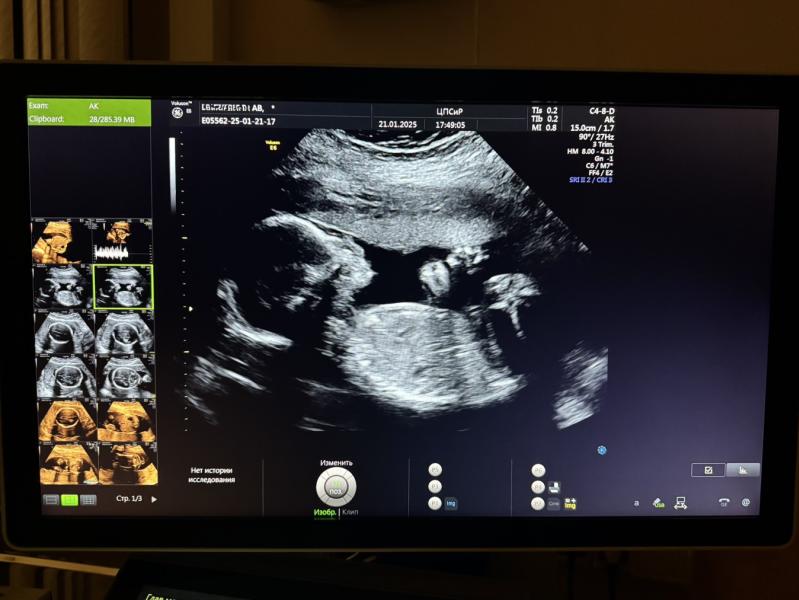

Прошли мы сегодня второй скрининг!

Я сегодня еле выпросила просто с экрана сфотографировать😁